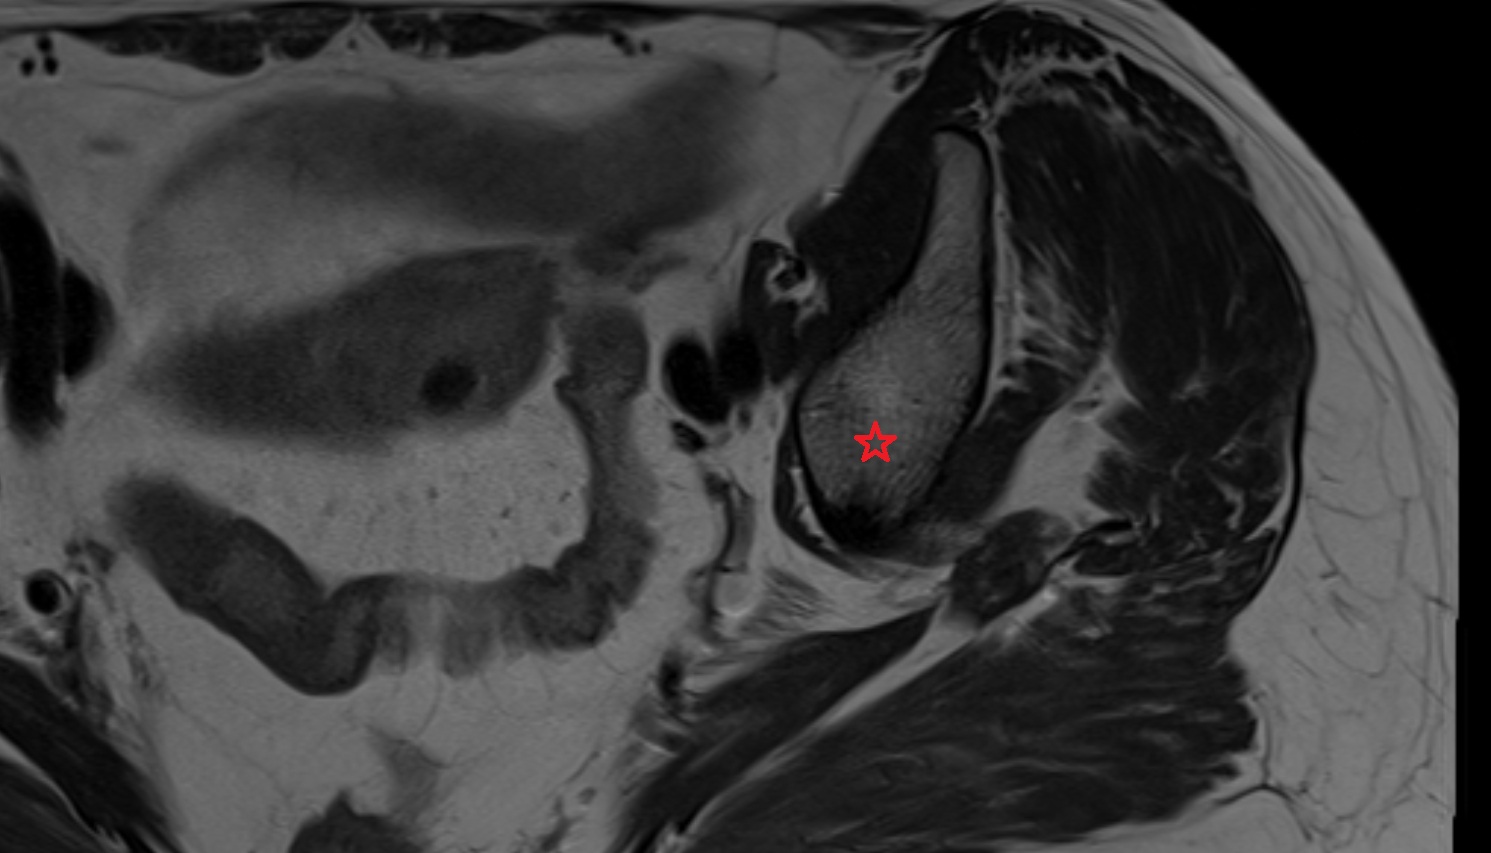

- Uterus

- Ovaries

- Right ovary

- Left ovary